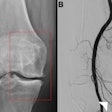

EVT is a minimally invasive image-guided surgical procedure used to dissolve blood clots in stroke patients, and thus restore blood flow (reperfusion) to prevent further brain damage. Recent clinical trials have provided robust evidence that the procedure improves functional outcomes among patients with large vessel occlusion (LVO), the authors wrote.

To address this knowledge gap, the group compared safety and efficacy outcomes in 126 patients older than 80 and 282 patients ages 80 and younger. Patients received EVT for acute ischemic stroke with large infarct at one of 25 German stroke centers between May 2015 and December 2021. Primary outcomes of the study were independent ambulation and mortality rates after 90 days.